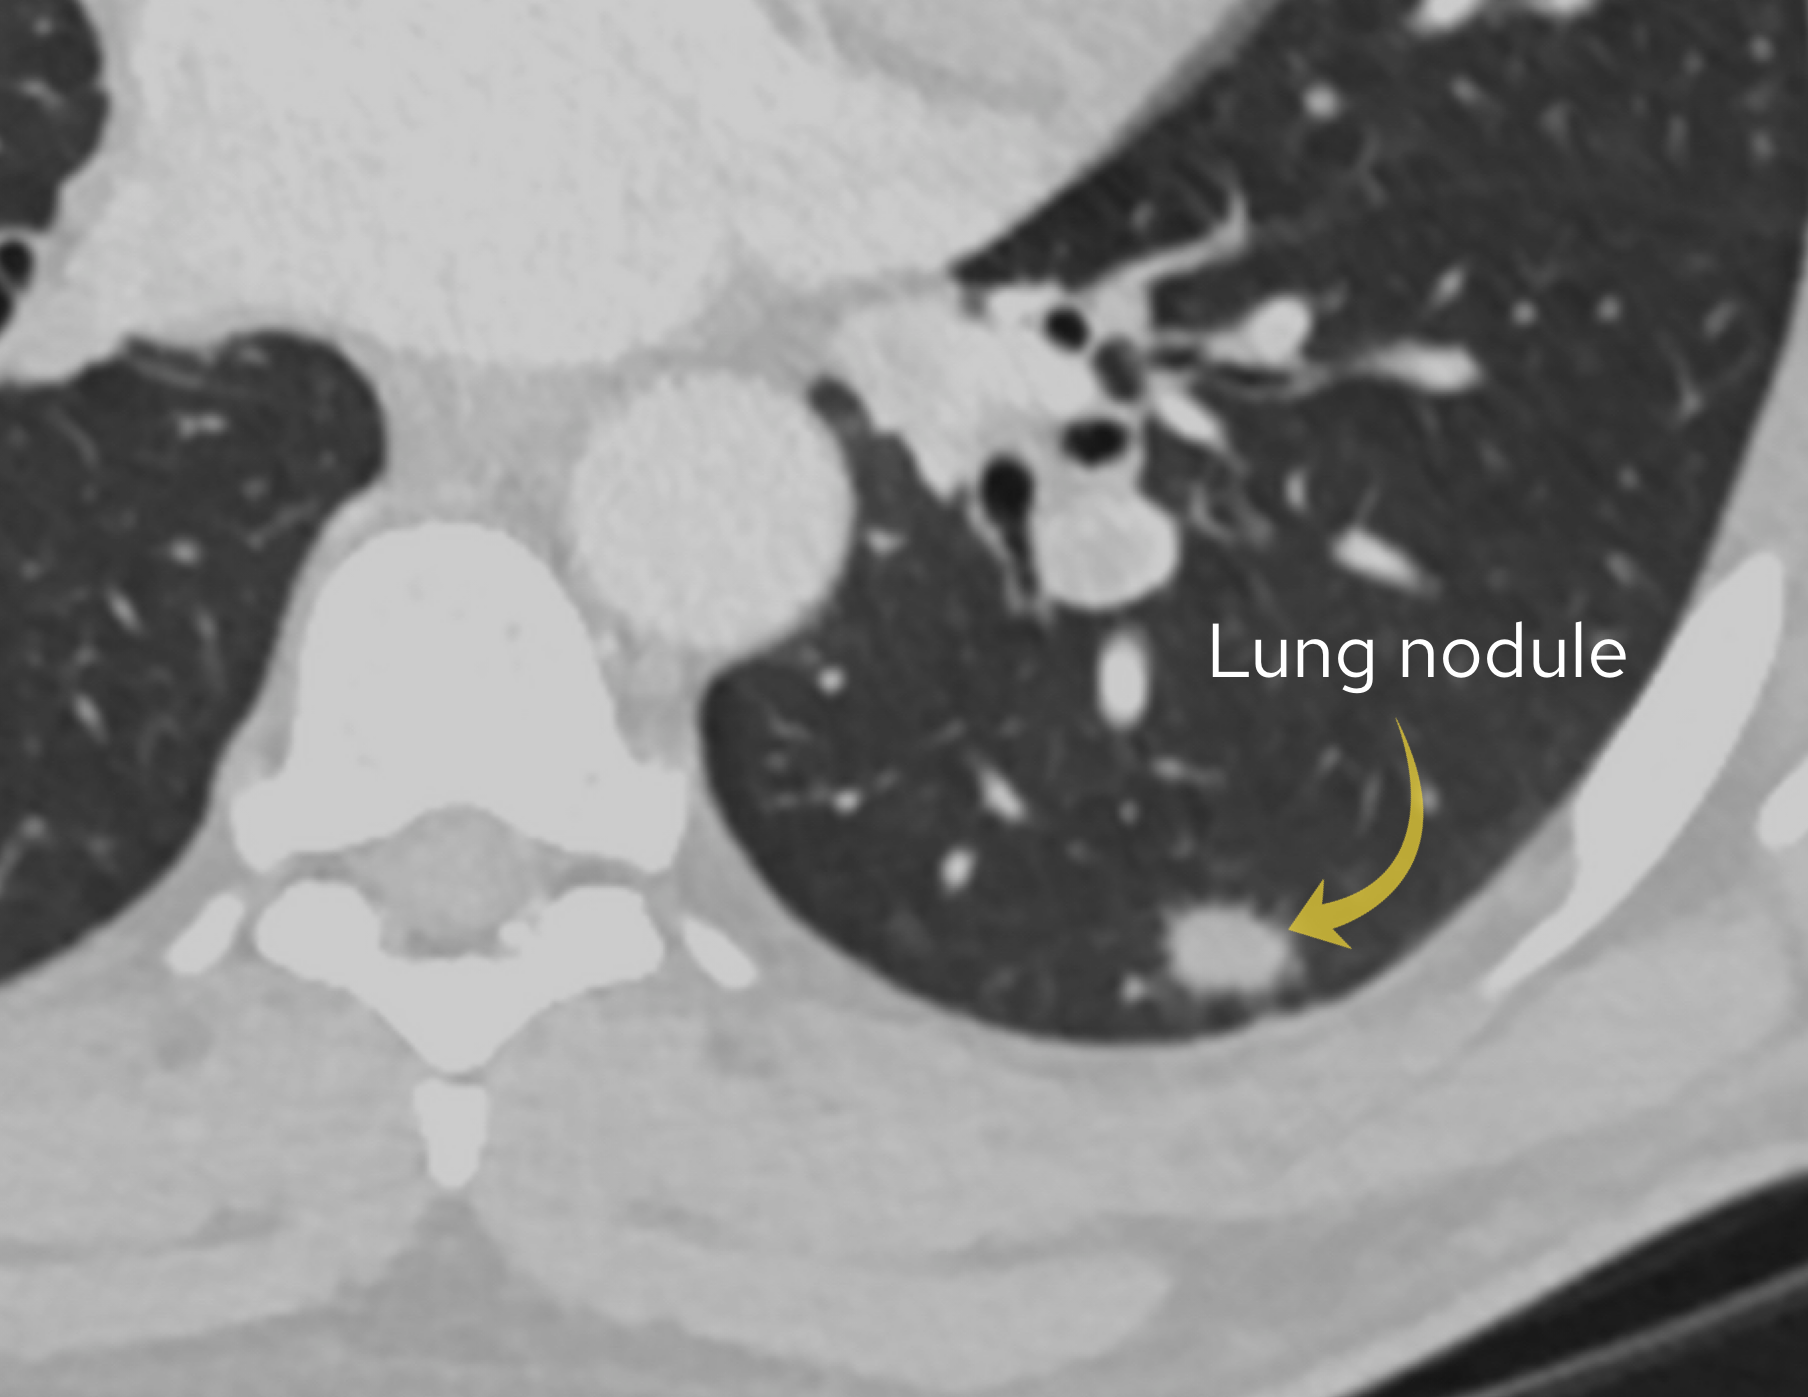

Case 8

A male in his 40s presents with chest pain. Here is a post contrast CT of his thorax.

Tap the first icon on the left to scroll.

What best describes the main scan finding? Choose one from the following options: